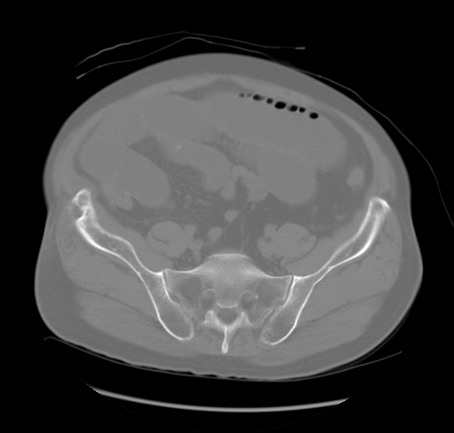

症例20(横断像)

【症例】 60歳代男性

【主訴】 腹部膨満、嘔吐

【現病歴】5日前頃より倦怠感を認め食事量減少し4日前の朝嘔吐、食事摂取困難となった。 3日前近医受診し点滴施行され整腸剤などを処方された。 当日他院を受診し、腹部膨満著明、炎症反応の上昇(CRP10.8、WBC11200)あり、紹介受診となる。

【身体所見】 意識JCS1 受け答えがはっきりしないBP 111/57mHg、 P 67bpm、、BT35.2°C、SpO2 97%(RA)、 腹部:膨隆、打診で鼓音あり、全体的に圧痛有り、腸蠕動音(-)、反跳痛ははっきりせず。

【データ】WBC 11400、CRP 14.20